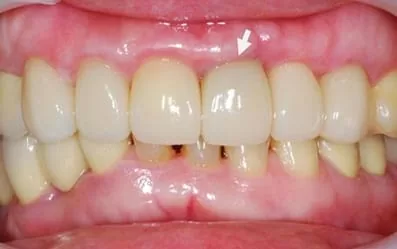

治療前:左上門牙疼痛、動搖,牙齦周圍有一圈黑黑的發炎。

一周後回診拆線,周圍牙齦長得非常漂亮。

二個半月後,換成新的臨時牙套,並進行牙齦塑型。

製作全瓷冠,是不是完全看不出來曾經接受2顆植牙呢!